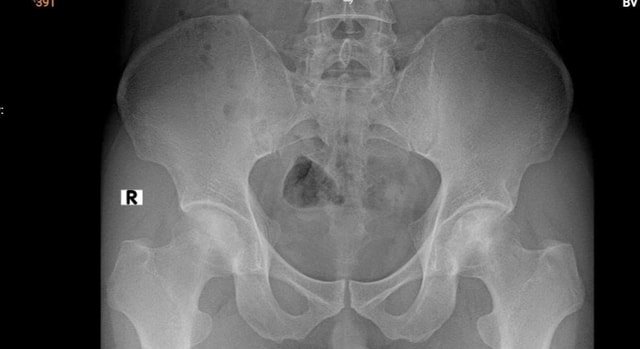

Kết quả chụp MRI cho thấy phần chỏm xương cánh tay trái bị hoại tử, ổ hoại tử lan xuống vùng cổ và thân xương cánh tay. Khi chụp X-quang phần khớp háng nhận thấy dấu hiệu hoại tử vô mạch chỏm xương đùi hai bên độ 2 theo ficat và alert (tình trạng tế bào xương ở chỏm xương đùi chết đi do mất nguồn cung cấp máu).